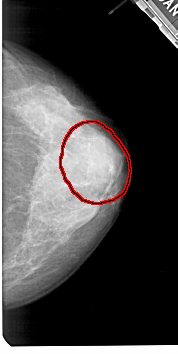

FILE: A_1425_1.RIGHT_CC.OVERLAY

TOTAL_ABNORMALITIES 1

ABNORMALITY 1

LESION_TYPE MASS SHAPE OVAL MARGINS OBSCURED

ASSESSMENT 4

SUBTLETY 3

PATHOLOGY BENIGN

TOTAL_OUTLINES 1

BOUNDARY